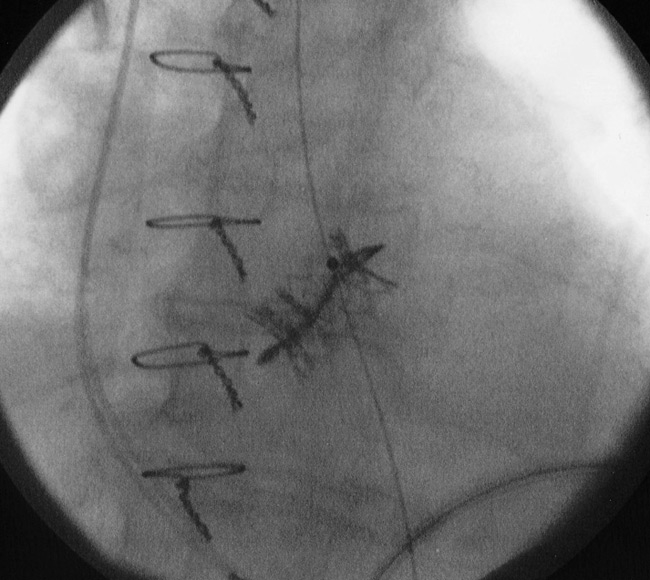

Figure 5

Image taken from the fluoroscopy system showing a transapical valve-in-valve procedure (a 23 mm SapienTM THV into a degenerated 23 mm Mitroflow bioprosthesis).

With regard to redo aortic valve surgery, in a few experienced cardiac centres it has recently become routine to perform “valve-in-valve” (VinV) procedures in case of degenerated aortic bio-prostheses in high-risk patients. In fact, the VinV strategy was developed to avoid high-risk redo cardiac surgery in old patients with degenerated valves, and is based on the implantation of a sized stent-valve into the stented or stentless diseased bio-prosthesis (the recommended minimal bio-prosthesis diameter for the transapical implantation of an Edwards Sapien™ stent-valve is 23 mm), and the latest postoperative clinical results are satisfactory [34, 35] (fig. 5). However the transcatheter VinV remains “off-label” and further clinical investigations are recommended.